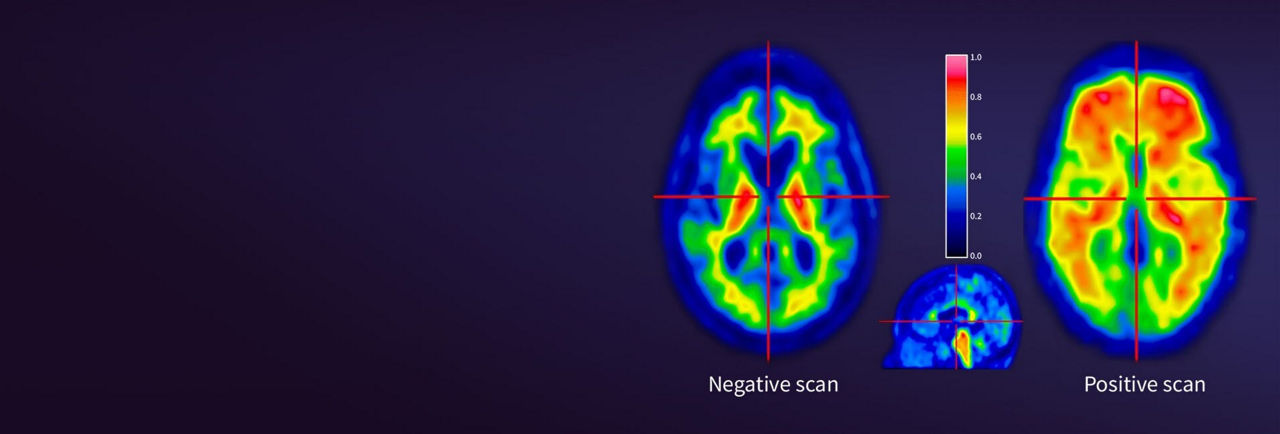

Vizamyl™ is a radioactive diagnostic agent indicated for PET imaging of the brain to estimate β-amyloid neuritic plaque density in adult patients with cognitive impairment.